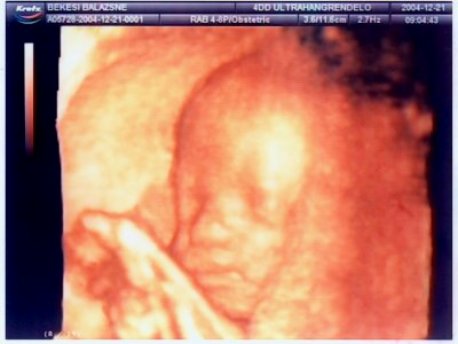

Hihetetlen, hogy tényleg mennyire látszanak a baba vonásai. Teljesen fel lehet ismerni az uh-on. Hála a tudománynak.